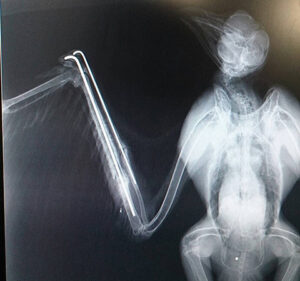

風が強く吹いた翌日、右の橈尺骨を骨折したトビが保護されました。明らかに元気が無く、今にも死んでしまいそうでした。また、レントゲン検査で骨折した部位に散弾が見つかり、被弾していたことが分かりました。野生動物と人の軋轢を目の当たりにした瞬間でした。

緊急手術で骨折した腕をつなぎ、散弾も摘出しました。このまま順調に回復してくれることを祈るばかりです。

※腰部にある散弾は尾羽に付着していたもの